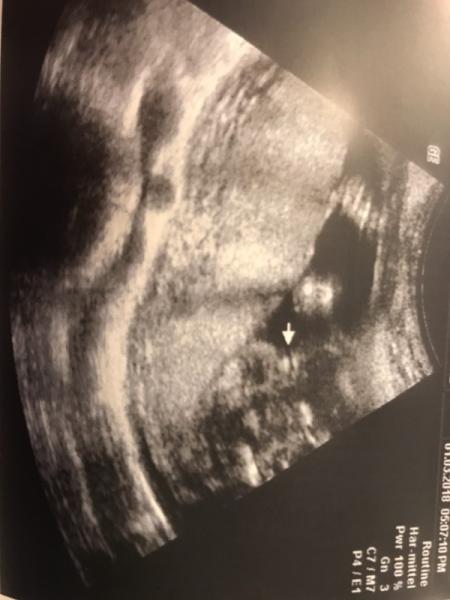

Hallo ihr Lieben, ich habe letzte Woche in der 21.SSW das lange ersehnte Outing bekommen,dass wir ein kleines Mädchen bekommen werden.Ich muss ehrlich zugeben,dass ich mir das sehnlichst gewünscht habe !Man hört ja aber immer mal wieder,dass aus Mädels dann doch noch Jungs werden...Meine FÄ war sich sicher,dass es eindeutig ein Mädchen ist..Was meint ihr?Könnte sich da noch was ändern?Bild ist angefügt.Danke fürs anschauen! Lg cassie

Bild zu Sicheres Outing? - Schwanger - wer noch? Rund um die Schwangerschaft

Das Geschlecht wird sich wohl nicht mehr ändern, das steht fest Der Pfeil zeigt doch wunderbar auf die Schamlippen, wieso vertraust Du Deinem Arzt nicht ?